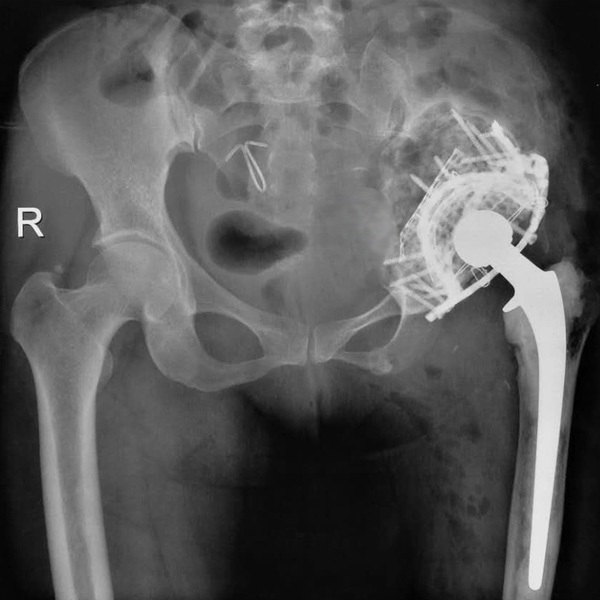

髖關(guān)節(jié)翻修

患者蘇某,女性,11年前因“左髖關(guān)節(jié)屈曲攣縮畸形”行左側(cè)人工全髖關(guān)節(jié)置換,近來感覺左髖關(guān)節(jié)疼痛,不敢行走,經(jīng)“攜生醫(yī)療平臺(tái)”就診于哈......